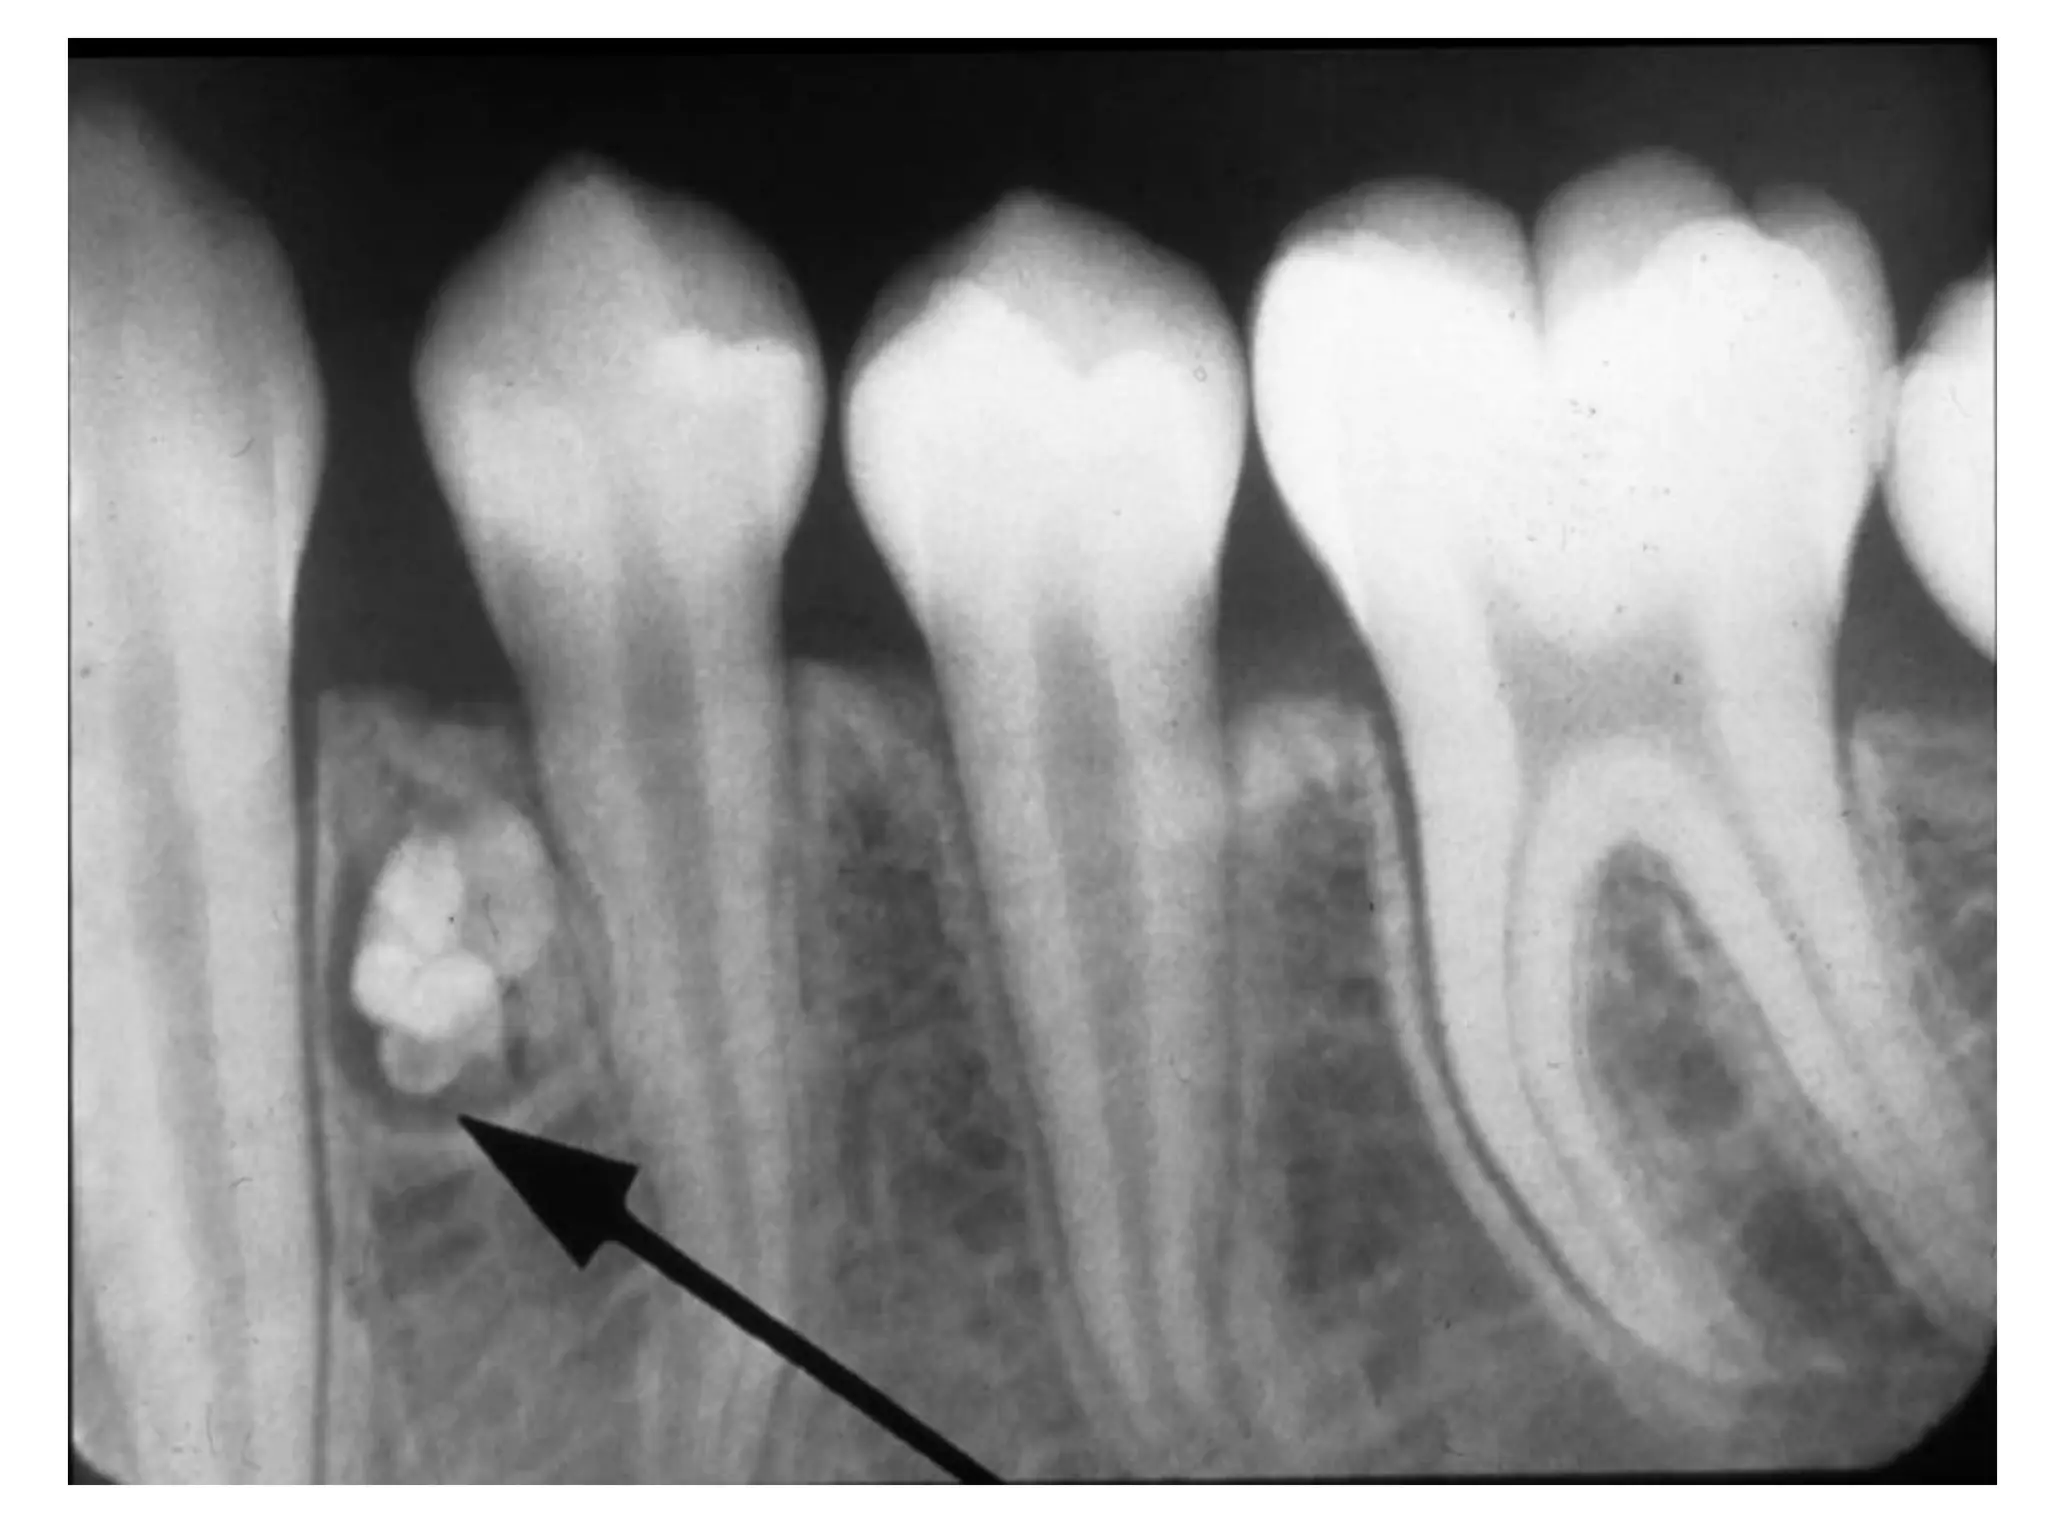

X quang:

 Sôùm: thaáu quang, ñöôøng vieàn roõ, nhaün.

 Muoän: caûn quang roõ.

 Daïng keát hôïp cho thaáy hình daïng raêng roõ

raøng trong khi daïng phöùc hôïp laø moät khoái caûn

quang ñoàng nhaát khoâng coù hình daïng raêng.

 U raêng coù theå caûn trôû raêng vónh vieãn moïc vaø luùc ñoù

u thöôøng ñöôïc phaùt hieän khi “tìm” raêng thieáu treân X

quang.

U raêng

Giaûi phaãu beänh:

 U raêng keát hôïp (compound odontoma) goàm

men, ngaø vaø xeâ maêng saép xeáp thaønh hình

daïng raêng.